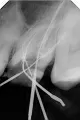

Мне прочищали каналы и клали лекарство в зуб шестерку, ставили временную пломбу. Все эти два месяца при пружинистой ходьбе в голове раздавался звук, как часы. И сейчас вкрутили штифт для культи под коронку в канал, все каналы запломбировали, а звук все равно есть.

Откровенно говоря, нет. Но штифт — неправильная конструкция, в этом случае стоит показаться более профессиональному стоматологу.

Если Вы выложите снимок, я постараюсь Вам помочь.